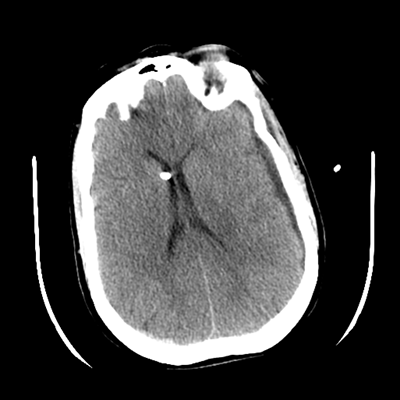

The patient goes down to CT. The following images are obtained. The subdural fluid collection is stable, as is the ventricular caliber.

NCHCT

Starting with the non-contrast head CT, we can appreciate that there's actually not much residual subarachnoid blood at all; it's essentially all resorbed already (and cleared through the EVD). The ventricular caliber is stable. With the CTA head (for convenience's sake, the MIPs were shown), it's subtle, but we can see that the PCAs on each side are not as smooth and regular. The right MCA, starting at the bifurcation, also becomes narrower. This is [radiographic] vasospasm. Now, looking at the CT perfusion-- specifically, the Tmax (MTT) map that were selected-- there's clearly some abnormality within the bilateral cerebellar hemispheres and occipital lobes. Not a lot, but it's there. Delving further into this map, we can appreciate that the areas of abnormality are mainly green, signifying that these areas have Tmax > 6 seconds. This is the threshold that is specific, not sensitive, for vasospasm.